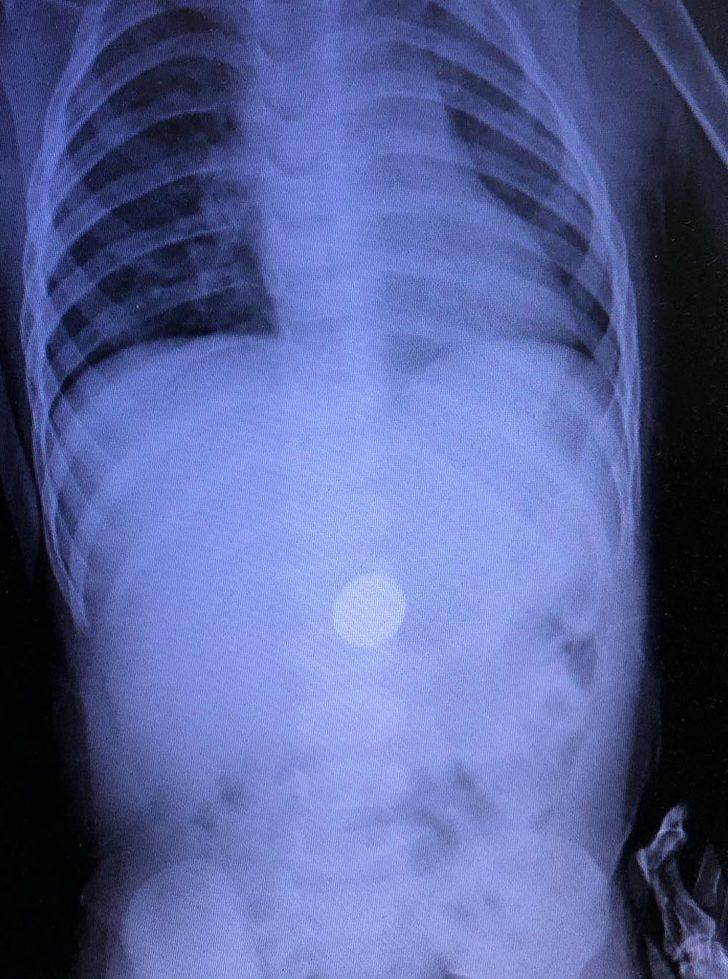

Zonguldak Kadın Doğum Çocuk Hastalıkları Hastanesi'ne 16 Ocak'ta başvuran aile, doktorlara çocuklarının madeni para yuttuğunu söyledi. Dr. Sertaç Akman, çekilen röntgende E.İ. isimli erkek çocuğun midesindeki 25 kuruşluk madeni parayı tespit etti. E.İ.'nin yapılan muayenesinde madeni paranın yemek borusuna zarar vermediği anlaşıldı. Doktorlar, gerekli tetkikleri yaptıktan sonra E.İ.'nin parayı doğal yollarla çıkarması için taburcu edip evine gönderdi. Takibe alınan E.İ.'nin normal yolla parayı çıkaramaması halinde endoskopi veya ameliyat gibi farklı yöntemlerle paranın çıkarılabileceği öğrenildi.